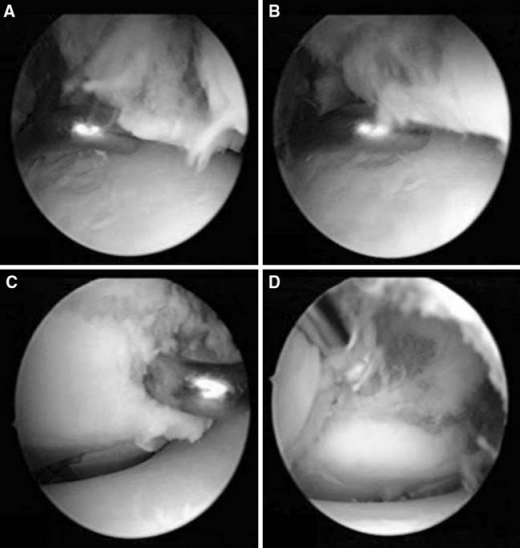

移位 > 2 mm 的骨折需要考虑手术治疗。包括闭合复位经皮克氏针或空心螺钉固定、切开复位内固定、关节镜辅助下复位固定。常见的内固定方式有克氏针和空心螺钉。内固定可跨骺板,因为 Tillaux 骨折常为青少年,骨骼接近成熟,因此穿过骨骺很少会发生双下肢不等长等情况,一般愈后较好。